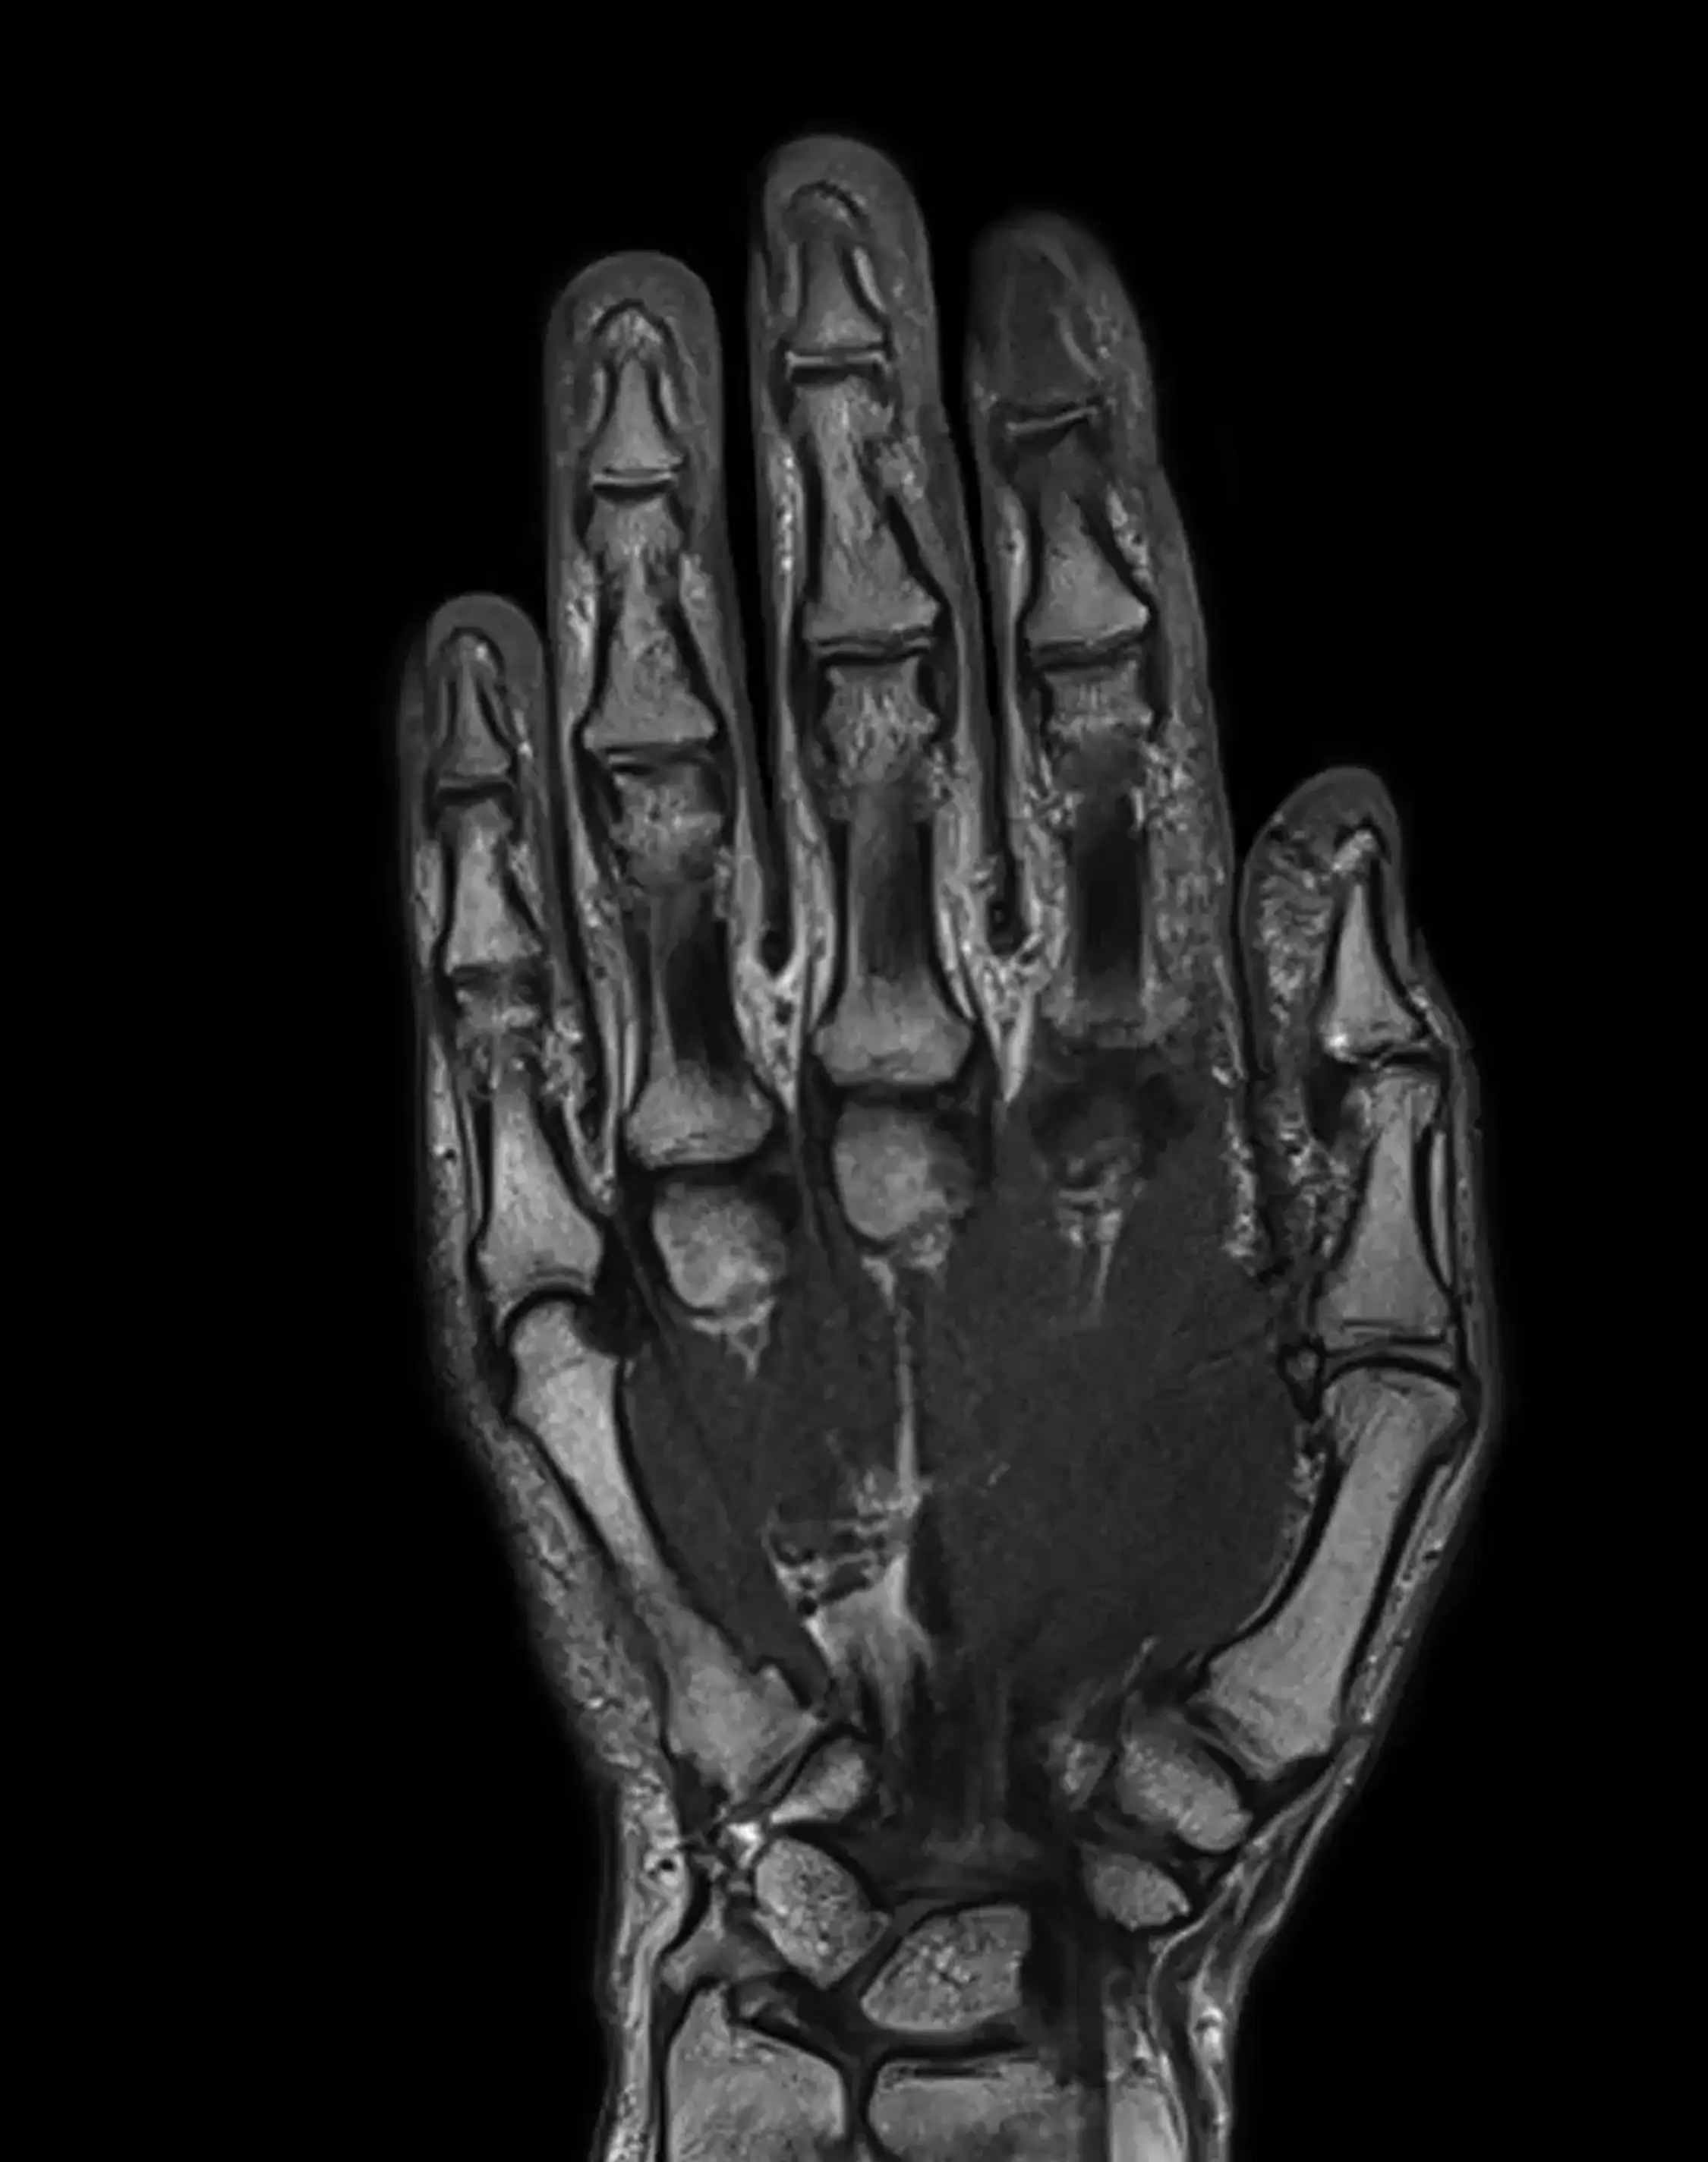

МРТ кисти

Помимо лучезапястного сустава, визуализируются структуры запястья, пястные и фаланговые, включая сочленения, сухожилия, мягкие ткани.